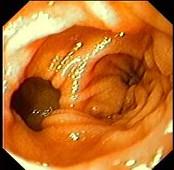

女性,45岁。腹部饱胀不适2年余。表情自然,皮肤无黄染,未见蜘蛛痣,巩膜无黄染。腹平坦,腹肌软,全腹无压痛反跳痛,肝脾肋缘下0.5cm,胃镜检查如下图,诊...

问题 女性,45岁。腹部饱胀不适2年余。表情自然,皮肤无黄染,未见蜘蛛痣,巩膜无黄染。腹平坦,腹肌软,全腹无压痛反跳痛,肝脾肋缘下0.5cm,胃镜检查如下图,诊断为 ( )

选项 A.十二指肠憩室 B.十二指肠溃疡 C.十二指肠炎 D.十二指肠穿孔 E.十二指肠雍滞症

答案 A